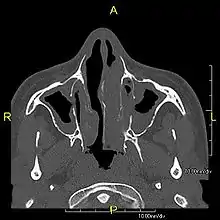

Complications | Chronic recurrent respiratory infections, including sinusitis, bronchitis, pneumonia, and otitis media.[2] |

Around 80% of people with primary ciliary dyskinesia experience respiratory problems beginning within a day of birth. Many have a collapsed lobe of the lung and blood oxygen low enough to require treatment with supplemental oxygen.[1] Within the first few months of life, most develop a chronic mucus-producing cough and runny nose.[1] The main consequence of impaired ciliary function is reduced or absent mucus clearance from the lungs, and susceptibility to chronic recurrent respiratory infections, including sinusitis, bronchitis, pneumonia, and otitis media. Progressive damage to the respiratory system is common, including progressive bronchiectasis beginning in early childhood, and sinus disease (sometimes becoming severe in adults). However, diagnosis is often missed early in life despite the characteristic signs and symptoms.[2] In males, immotility of sperm can lead to infertility, although conception remains possible through the use of in vitro fertilization, there also are reported cases where sperm were able to move.[8] Trials have also shown that there is a marked reduction in fertility in females with Kartagener's syndrome due to dysfunction of the oviductal cilia.[9]

Many affected individuals experience hearing loss and show symptoms of otitis media which demonstrates variable responsiveness to the insertion of myringotomy tubes or grommets. Some patients have a poor sense of smell, which is believed to accompany high mucus production in the sinuses (although others report normal – or even acute – sensitivity to smell and taste). Clinical progression of the disease is variable, with lung transplantation required in severe cases. Susceptibility to infections can be drastically reduced by an early diagnosis. Treatment with various chest physiotherapy techniques has been observed to reduce the incidence of lung infection and to slow the progression of bronchiectasis dramatically. Aggressive treatment of sinus disease beginning at an early age is believed to slow long-term sinus damage (although this has not yet been adequately documented). Aggressive measures to enhance clearance of mucus, prevent respiratory infections, and treat bacterial superinfections have been observed to slow lung-disease progression. The predicted incidence is 1 in approximately 7500.[10]